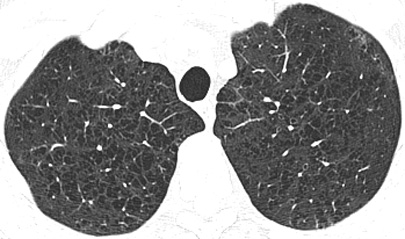

CT/HRCT

• More sensitive than chest radiography

• Emphysematous holes usually have no discernable wall

• Central artery may remain visible surrounded by destroyed lung

• Objectively measured by assuming that lung with a threshold HU < -960 is emphysematous lung